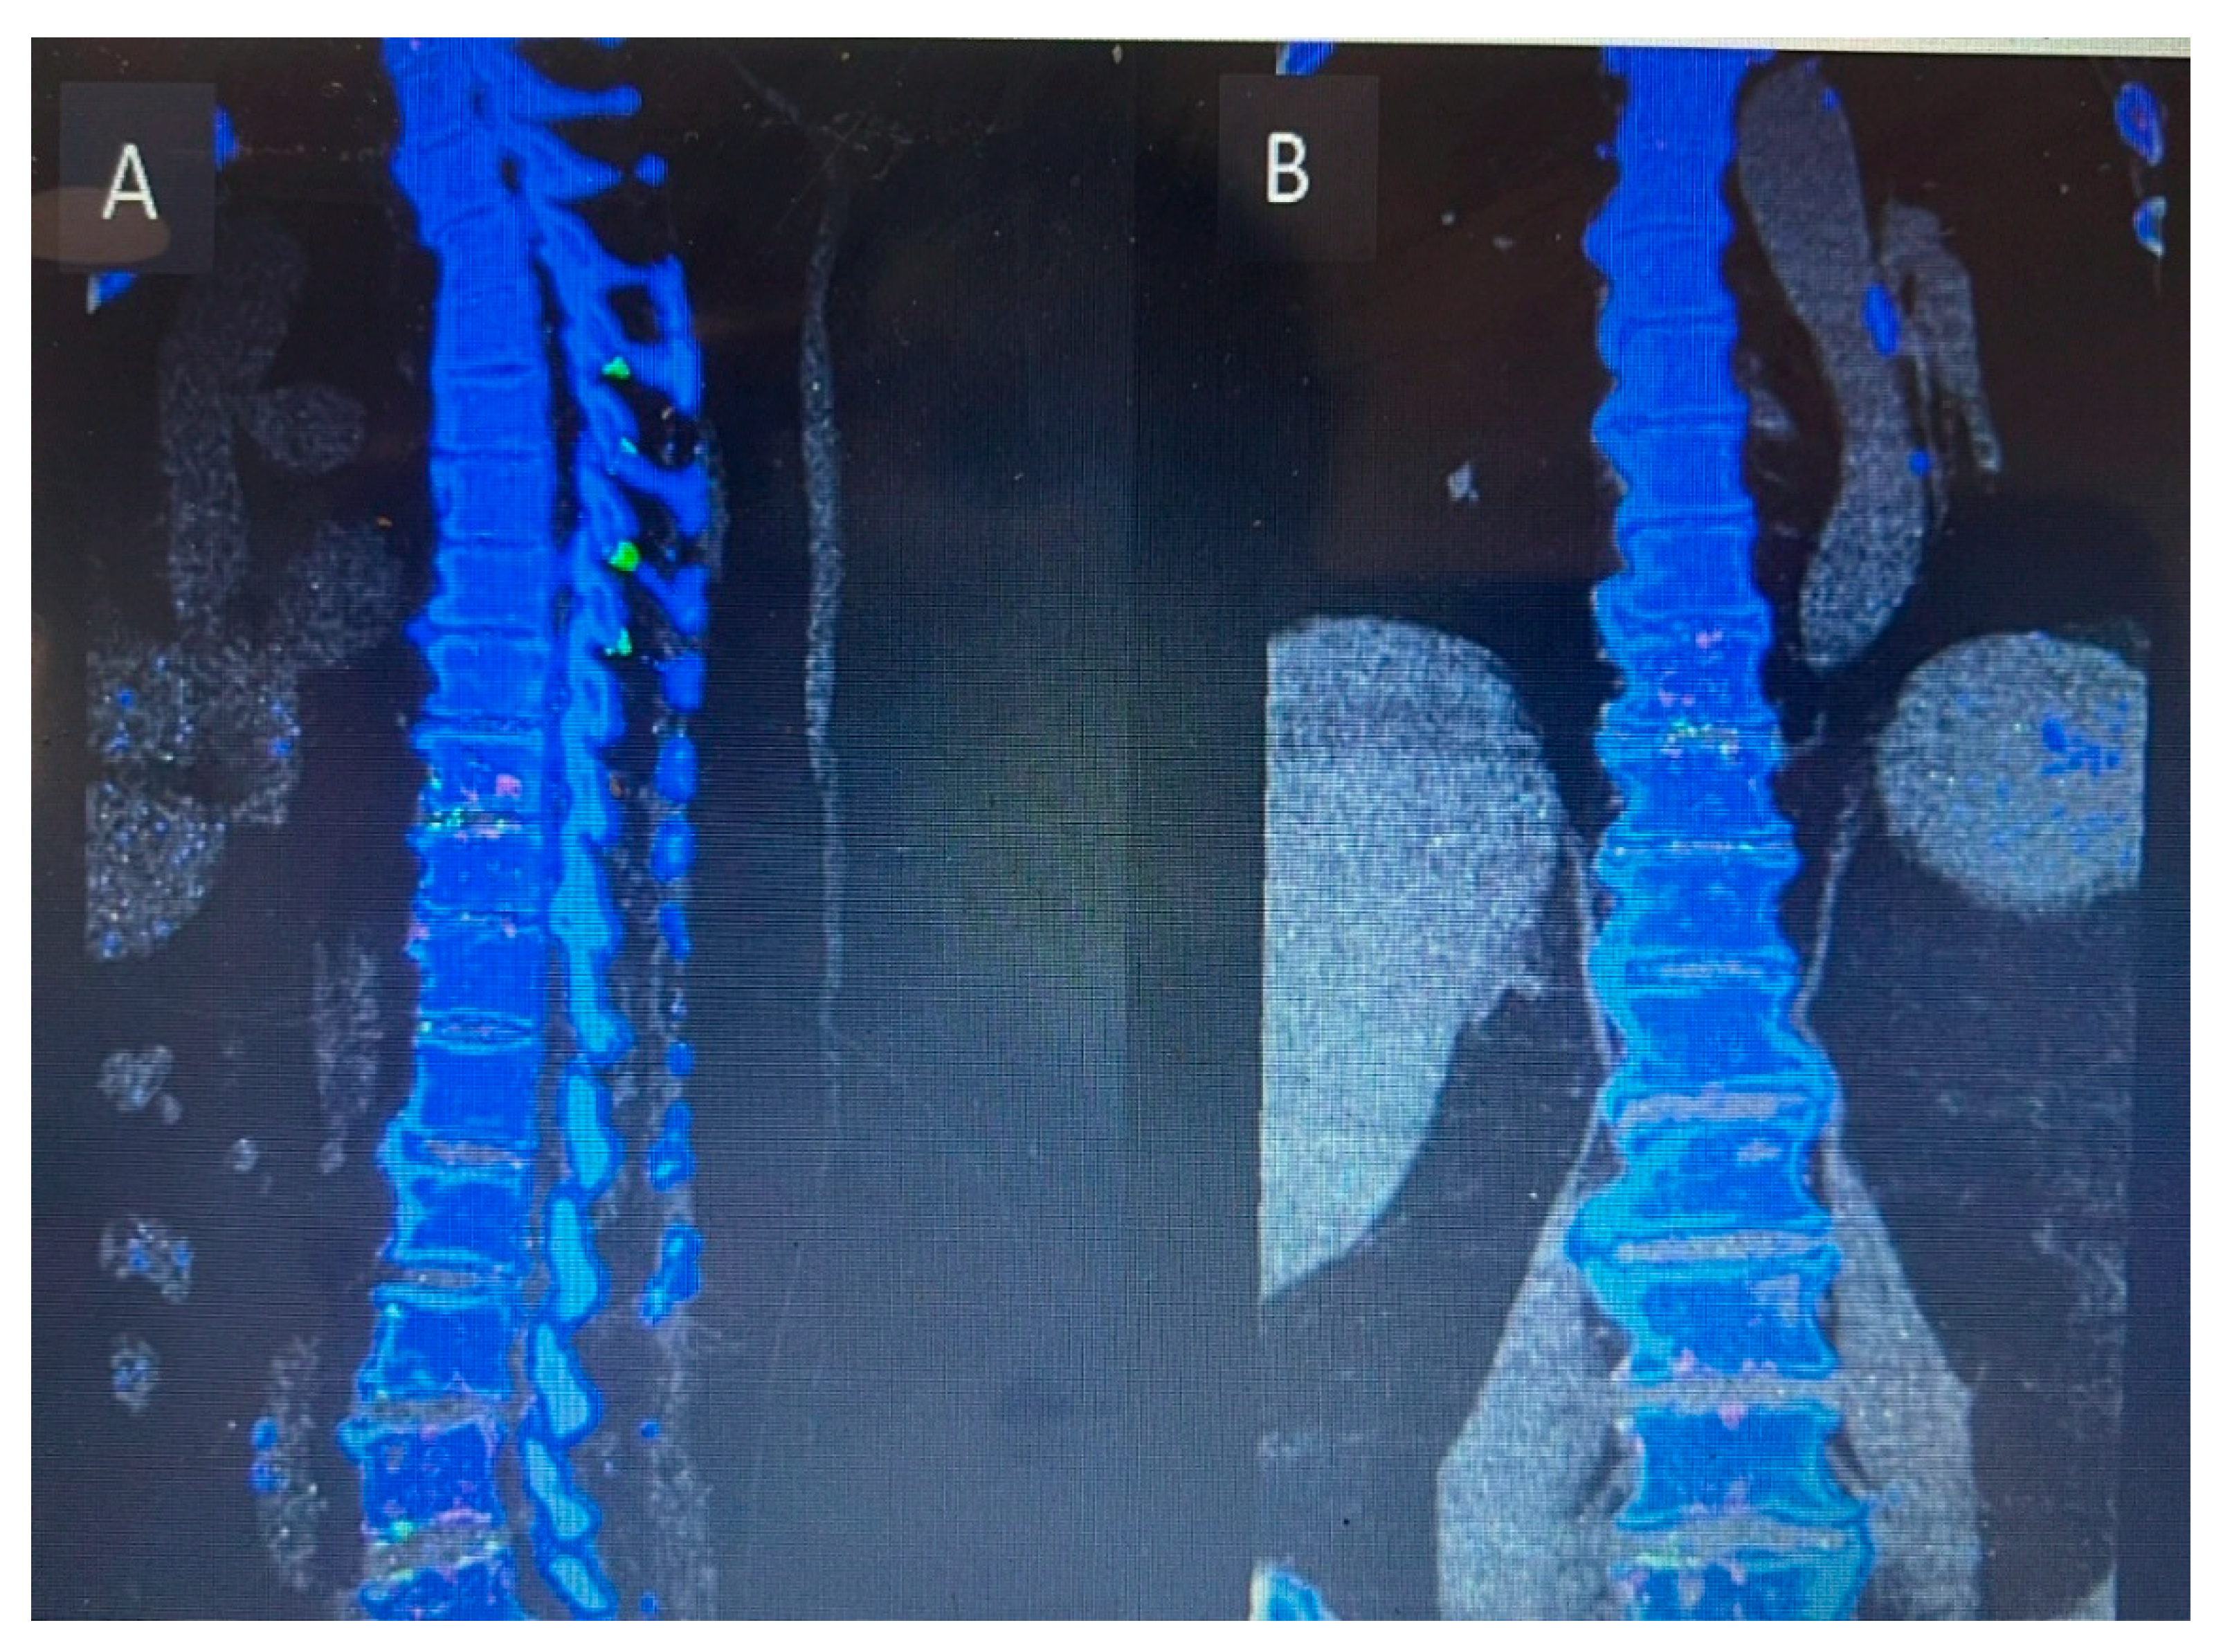

CT C Spine: Ossification of the right-side ligamentum flavum noted at C4/C5 and C5/C6 levels, with associated spinal canal narrowing, more severe at C4/C5.

Figure 1. Preoperative sagittal (A) and axial (B) CT cervical spine showing calcific deposit at the cervical 4 level causing spinal stenosis.